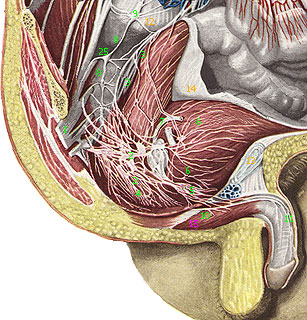

Срамной (половой) нерв(n. pudendus (pudendalis); срамное сплетение, plexus pudendus; S1-S4) представляет собой каудальный (хвостовой) отдел крестцового сплетения (начало: plexus sacralis) и связан с ним несколькими ветвями. Нерв лежит под нижним краем грушевидной мышцы на передней поверхности копчиковой мышцы; по его передней поверхности проходят в продольном направлении латеральные крестцовые сосуды (vasa sacralia lateralia).

Срамной нерв связан с крестцовым сплетением и нижележащим копчиковым сплетением, а также несколькими нервными стволиками с вегетативным нервным сплетением (нижним) подчревным сплетением (plexus hypogastricus (inferior)). Своими ветвями срамной нерв принимает участие в иннервации внутренних органов полости малого таза, наружных половых органов, мышц промежности и кожи области промежности, слизистую оболочку мочеиспускательного канала. Топографически нерв можно разделить на две части: внутритазовую и внетазовую (промежностную).

Ветви внутритазовой части срамного нерва

1. Мышечные ветви отходят от нерва в полости малого таза и направляются к мышце, поднимающей задний проход (m. levator ani), и копчиковой мышце (m. coccygeus) (эту мышцу может иннервировать ветвь, общая с m. levator ani).

2. Средние прямокишечные нервы, соединяясь с ветвями подчревного сплетения, подходят к той части прямой кишки, которая располагается выше m. levator ani; ряд нервных стволиков входит в толщу этой мышцы.

3. Нижние пузырные нервы, так же как и предыдущие, соединяются с ветвями подчревного сплетения и следуют к области дна мочевого пузыря, к мышце, сжимающей мочевой пузырь (m. sphincter vesicae).

4. Влагалищные нервы, соединяясь с ветвями подчревного сплетения, направляются к верхним отделам влагалища.

Ветви внетазовой (промежностной) части срамного нерва

Срамной нерв выходит из полости малого таза в сопровождении медиально лежащих от него внутренних срамных сосудов (vasa pudenda interna), через щель под грушевидной мышцей. Далее он ложится на заднюю поверхность седалищной ости (spina ischiadica), огибает ее и, пройдя через малое седалищное отверстие (foramen ischiadicum minus), возвращается в полость таза, располагаясь ниже мышцы, поднимающей задний проход (m. levator ani), в седалищно-ректальном углублении (fossa ischiorectalis), где он идет по ее латеральной стенке, в толще фасции внутренней запирательной мышцы.

В седалищно-ректальном углублении срамной нерв делится на свои ветви:

· а) Нижние прямокишечные нервы (nn. rectales inferiores) располагаются наиболее медиально, следуют к промежностной части прямой кишки, наружному сфинкетру заднего прохода (m. sphincter ani externus) и к коже области заднепроходного отверстия.

· б) Промежностные нервы (nn. perineales) следуют в сопровождении сосудов промежности (vasa perinei) и являются наиболее поверхностным из концевых ветвей срамного нерва.

· в) Задние мошоночные нервы (nn. scrotales posteriorei) или задние губные нервы (nn. labiates posteriores) - поверхностно лежащая группа ветвей, направляющихся к коже области промежности и к коже задней поверхности мошонки (больших срамных губ); эти нервы соединяются с нижними прямокишечными нервами, а также с промежностными ветвями заднего кожного нерва бедра.

· г) Мышечные ветви - более глубоко располагающиеся нервные стволики, которые следуют к передним отделам наружного сфинкетра заднего прохода (m. sphincter ani externus), поверхностной поперечной мышцы промежности (m. transversus perinei superficialis), луковично-губчатой мышцы (m. bulbospongiosus) и к седалищно-пещеристой мышцаы (m. ischiocavernosus).

· д) Дорсальный нерв полового члена (n. dorsalis penis) или дорсальный нерв клитора (n. dorsalis clitoridis) является верхней ветвью срамного нерва. Он следует в сопровождении артерии полового члена (короткой ветви внутренней срамной артерии) по внутренней поверхности нижней ветви седалищной и лобковой костей и, проходя через мочеполовую диаграмму, ложится вместе с дорсальной артерией мужского полового члена (a. dorsalis penis) или клитора (clitoridis) на спинку мужского полового члена или клитора у женщин, где разветвляется на свои концевые ветви в коже и в пещеристых телах мужского полового члена, достигая его головки, а у женщин достигает больших и малых срамных губ. На своем пути нерв посылает стволики к m. transversus perinei profundus, m. sphincter urethrae membranaceae и к нервному пещеристому сплетению (plexus cavernosus penis (clitoridis)).

1 - крестцовое сплетение (plexus sacralis); 2 - нижнее подчревное (тазовое) сплетение, передняя часть (plexus hypogastricus inferior (pars ventralis)); 3 - нижнее подчревное (тазовое) сплетение, задняя часть (plexus hypogastricus inferior (pars dorsalis)); 4 - прямокишечное сплетение (plexus rectalis); 5 - простатическое сплетение (plexus prostaticus); 6 - мочепузырное сплетение (plexus vesicalis); 7 - семявыбрасывающепроточное сплетение (plexus deferentialis); 8 - симпатический (пояснично-крестцовый) ствол (truncus sympathicus (truncus lumbosacralis)); 9 - пояснично-крестцовый узел симпатического ствола (ganglion lumbosacrali trunci sympathici); 10 - срамной нерв (n. pudendus); 11 - правый дорсальный нерв полового члена (ветви) (n. dorsalis penis dexter); 12 - крестцовый мыс (promontorium; сакровертебральный угол); 13 - лобковый симфиз (symphysis pubica); 14 - брюшина (peritoneum); 15 - луковично-губчатая мышца (m. bulbocavernosus); 16 - нижние прямокишечные нервы; 17 - мышечные нервы срамного сплетения; 18 - промежностный нерв; 19 - ветвь промежностного нерва к предстатетльной железе; 20 - ветвь промежностного нерва к мошонке; 21 - правая луковично-мочеиспускательная железа мочеиспускательного канала; 22 - предстательная железа; 23 - мочевой пузырь; 24 - прямая кишка; 25 - крестцовый узел симпатического ствола (ganglion sacrali (trunci) sympathici)